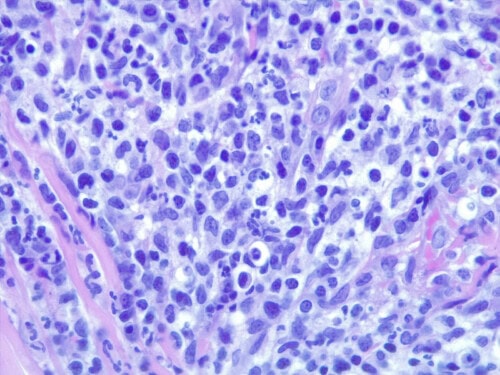

Un examen histopathologique est demandé au LAPVSO (Dr Frédérique DEGORCE). Les biopsies mettent en évidence des lésions surélevées focales en plaques, caractérisées par une une hyperplasie psoriasiforme, épidermique, avec spongiose, œdème des acanthocytes et une forte exocytose de granulocytes neutrophiles, évoluant en pustules granulocytaires sous et intra-cornées qui s’impétiginisent. Dans le derme sous-jacent un infiltrat forme une plage cellulaire d’allure lichénoïde, les cellules se collectant sous la membrane basale épidermique et entourant les apex folliculaires. L’infiltrat cellulaire est formé de granulocytes neutrophiles, de cellules histiocytoïdes et petits lymphocytes et de plasmocytes. Une vésiculation hydropique est présente à l’interface des structures épithéliales ainsi que quelques corps apoptotiques dans leur couche basale. Aucun élément figuré, ni parasitaire, ni fongique n’a été détecté sur les différents plans de section effectués, ni sur la réaction au PAS. (photos 5 à 8)

Photos 5 : HES*630 gros plan sur l’infiltrat cellulaire formé de granulocytes neutrophiles, cellules histiocytoïdes, lymphocytes et plasmocytes